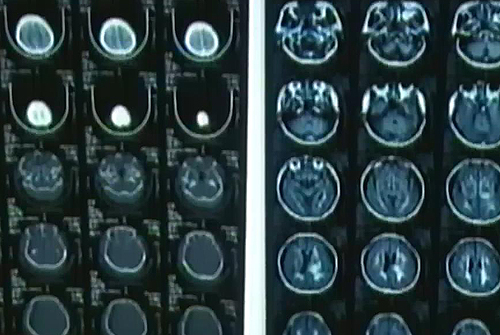

보통 뇌졸중은 노인성 질환으로 생각하기 쉽지만 최근 몇 년 사이 10대 청소년 뇌졸중 환자들이 급증하고 있다.

심지어 10세 미만의 뇌졸중 환자도 늘고 있다.

뇌혈관이 막히거나 터지면서 발생하는 뇌졸중은 제 때 치료받지 않으면 신체 일부가 영구히 마비될 수 있다.